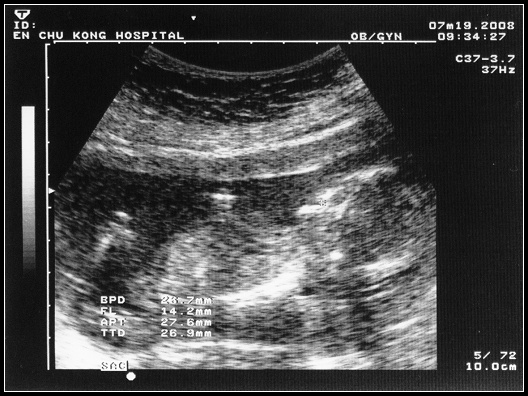

又到小球露臉的時候了,這次回診小球已經3個多月了,五官輪廓及四肢都已大致成形。隨著超音波探測器在肚皮上來回的滑動,看了小球的眼睛、嘴吧、心跳、雙手、雙腳和脊椎,很好,應該是個健康活潑的小寶寶。不過,小球的小雞雞呢?答案是小雞雞不見了,呵呵!

的確,有了小羽的我們會期待小球是弟弟,在醫生告知小球應該是女生時,當下有著些許的失落感!但,失落感很快就淹沒在開心的情緒裡,懷孕的爸媽都知道,寶寶的建康比啥都重要。隨著五官和四肢的一一呈現,我們和小球的距離又拉近了一些,滿心期待她的降臨。

看診後,和婆一直拿小球有沒有小雞雞這件事開玩笑,婆還說小球的小雞雞會不會被夾住了看不到,我想可能嗎?不過,醫生說再長大一點看會更確定,也就是說小球會小雞雞的機率並非是零。那~表示小雞雞話題會延續到小球的下次登場,看來就下回揭曉囉!